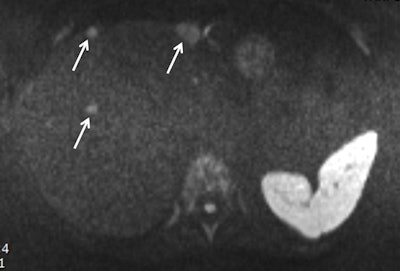

Obtained during a short protocol, this diffusion-weighted image shows a patient with conspicuous liver metastasis. The lesions are marked by arrows. Courtesy of Dr. Thomas Lauenstein. Originally published in the ECR Today newspaper."Hence, a dedicated first-time MRI exam of the liver could encompass more or different sequences than a follow-up exam or a surveillance exam of patients with a high-risk profile," he explained. "If we follow this strategy, examination time can be spared and more exams per time unit could be performed."